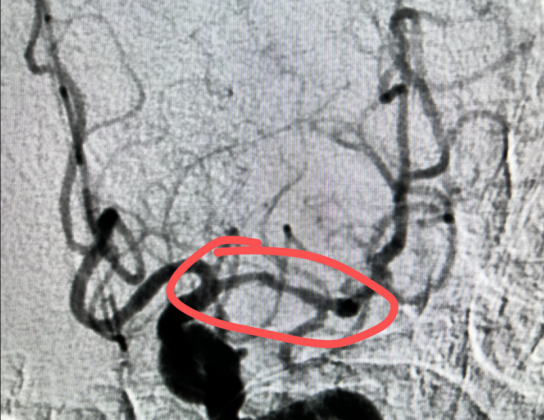

与家属沟通后,决定进行急诊脑血管造影,介入科黄绪鑫主任亲自穿刺,成功后证实:左侧大脑中动脉M1段闭塞,mTICI 0级。

(术中造影证实:左侧大脑中动脉闭塞,左侧大脑中动脉供血区无血流)